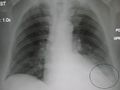

A chest X-ray showing a very prominent wedge shaped pneumonia in the right lung. | |

وعن طريق السماعة الطبية، يستطيع الطبيب أن يسمع أصواتًا مميزة آتية من الرئة تدل على وجود المرض. ويمكن لأشعة إكس (الأشعة السينية)، والاختبارات المعملية، أن تؤكد صحة التشخيص. أما تحديد نوع الميكروب المسبب للمرض، فإنه يتم عن طريق الاختبارات المعملية، إذ يقوم العامل الفني المتخصص بفحص عينة من بلغم المريض تحت المجهر. كما يعالج البلغم أيضًا بطرق مختلفة، حتى يمكن تنمية الكائن العضوي المُسبِّب للعدوى داخل المعمل، بحيث يمكن التعرف عليه.